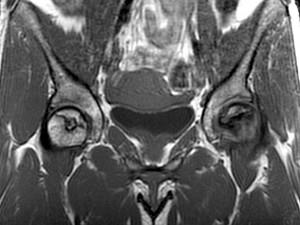

问题 女,34岁,双侧髋部疼痛,结合图像,最可能的诊断是 ( )

选项 A、股骨头缺血坏死 B、痛风 C、类风湿关节炎 D、髋关节退行性变 E、未见异常

答案 A